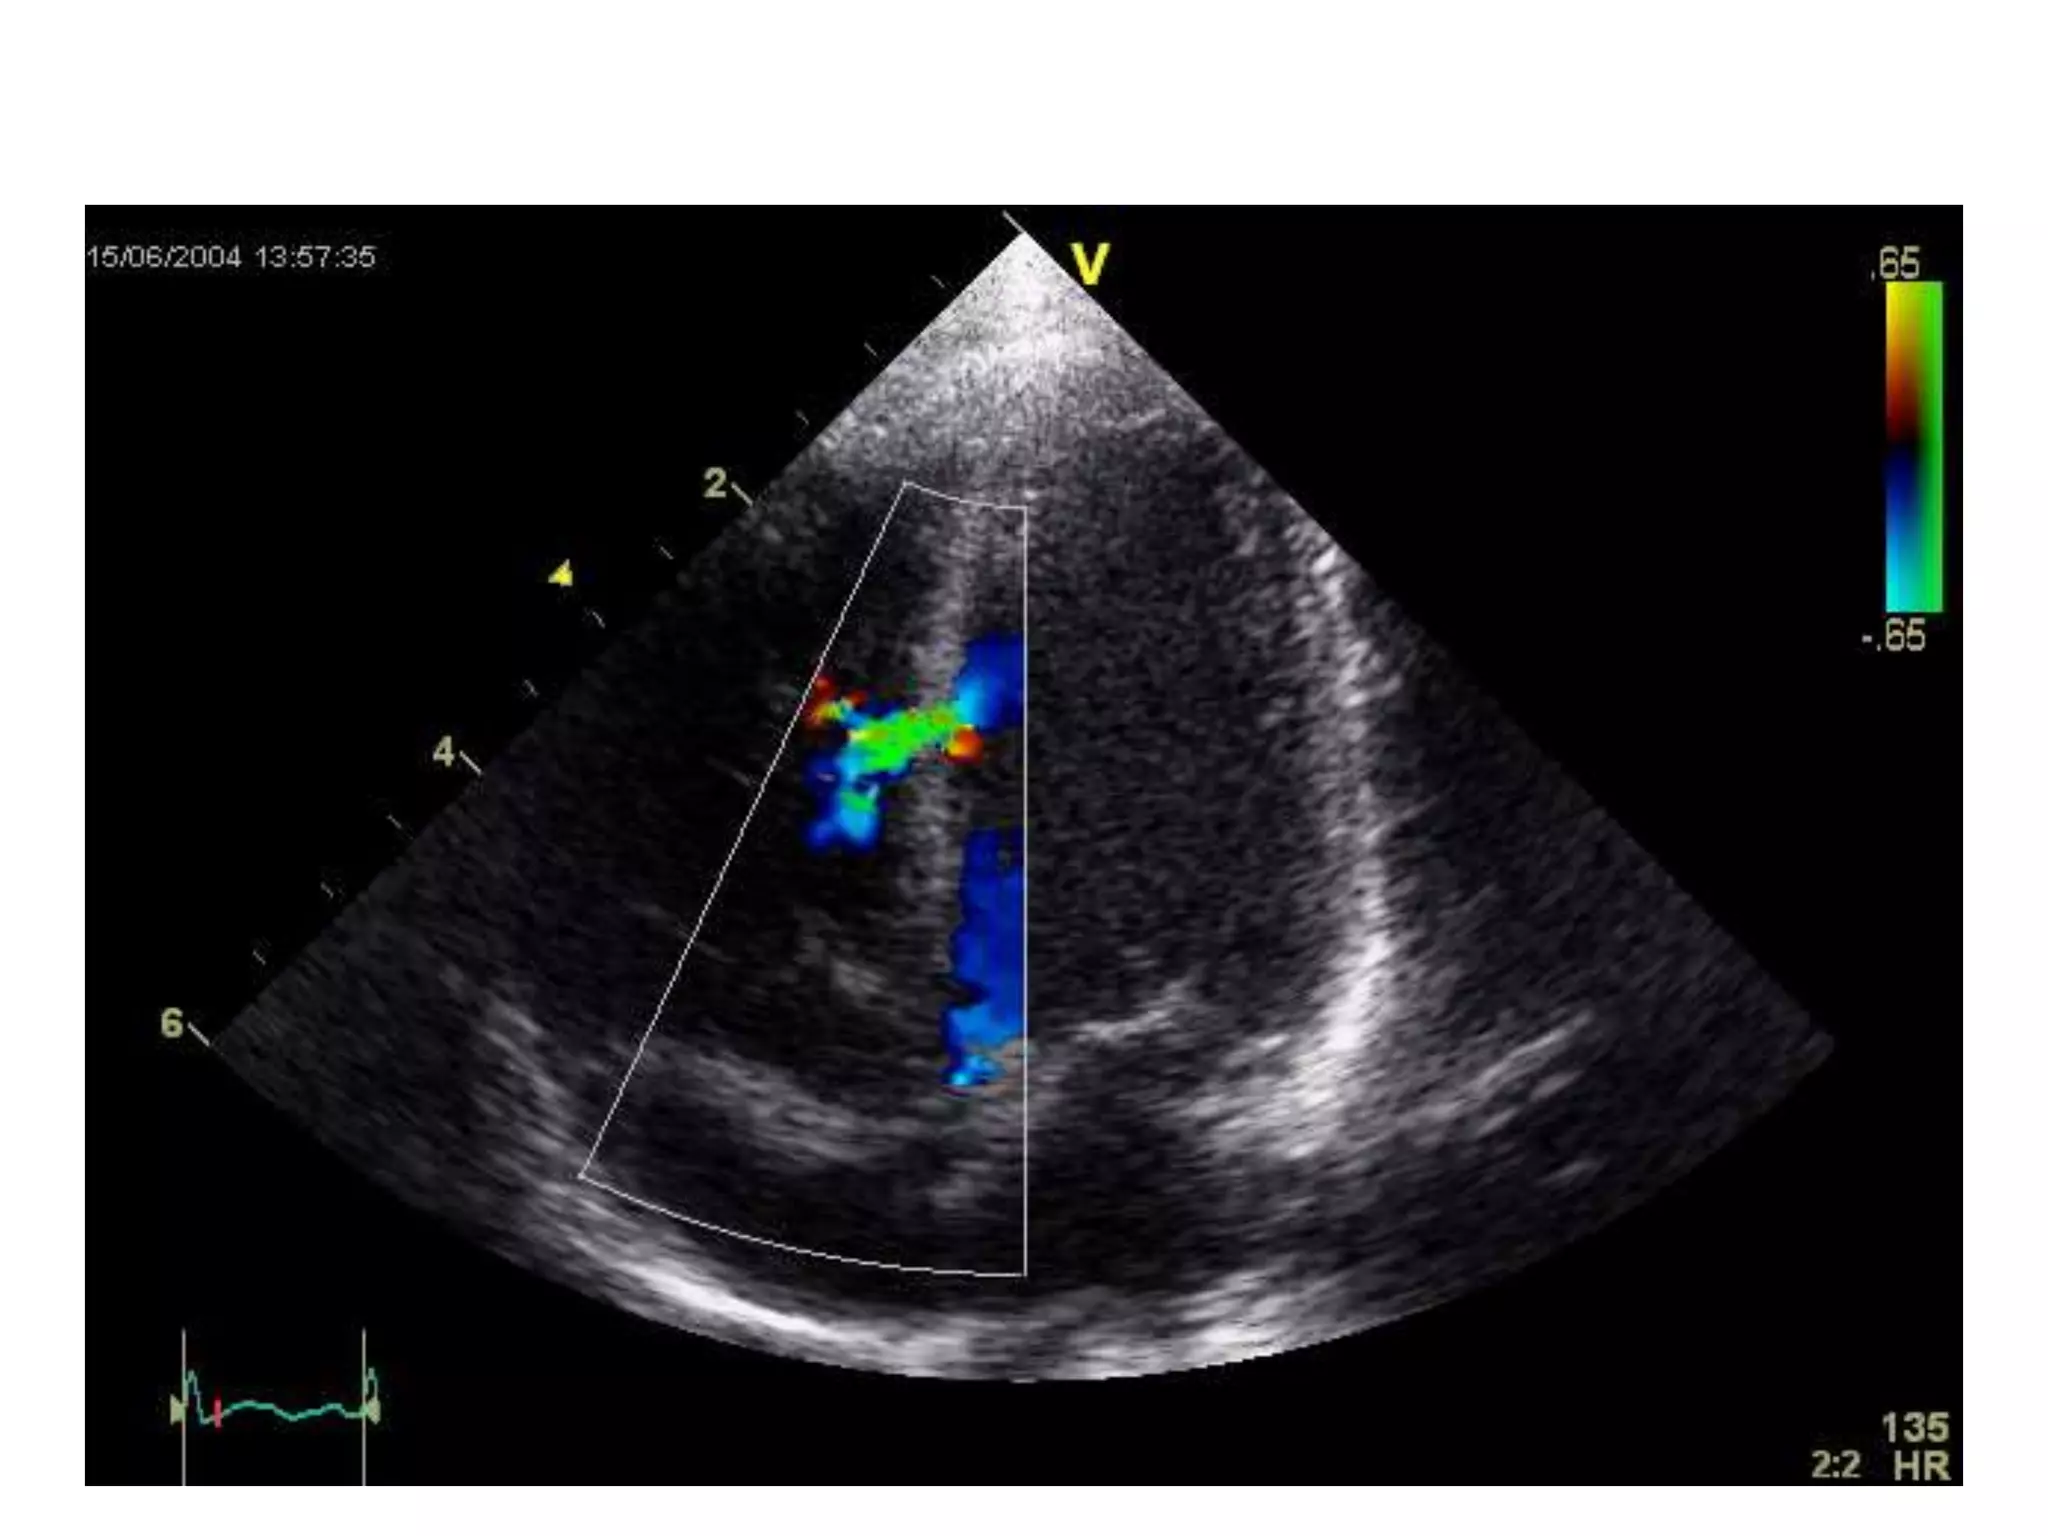

Colour flow mapping

• ● Assessment of

regurgitation and shunts.

Summary Of EchoModalities And Their Main Uses 2-D echo • ● Anatomy • ● Ventricular and valvular movement • ● Positioning for m-mode and doppler echo M-mode echo • ● Measurement of dimensions • ● Timing cardiac events Pulsed wave Doppler • ● Normal valve flow patterns • ● LV diastolic function • ● Stroke volume and cardiac output. Continuous wave • ● Severity of valvular stenosis • ● Severity of valvular regurgitation • ● Velocity of flow in shunts Colour flow mapping • ● Assessment of regurgitation and shunts.